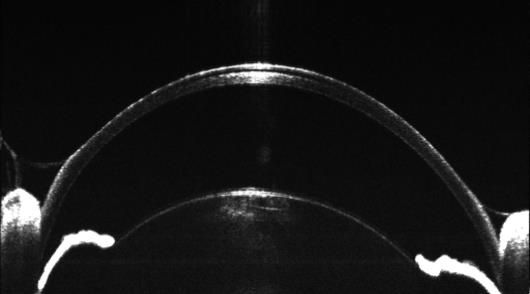

用于眼科动物模型的疾病筛查、病理学、药理学、药效学等方面研究。适用于各项眼科疾病、糖尿病、动脉硬化、高血压、干细胞等研究中视网膜结构的定量变化及定性分析。可对活体动物神经细胞,神经纤维层、微血管等微观结构改变进行早期、实时及长期无损伤的评估。

※ 1.6um高分辨率成像,实现更精准的病变及疗效评估;

4、用户自定义分层测量,实现脉络膜、感光细胞层更细分层次的厚度分析;

应用:眼节OCT成像及定量分析